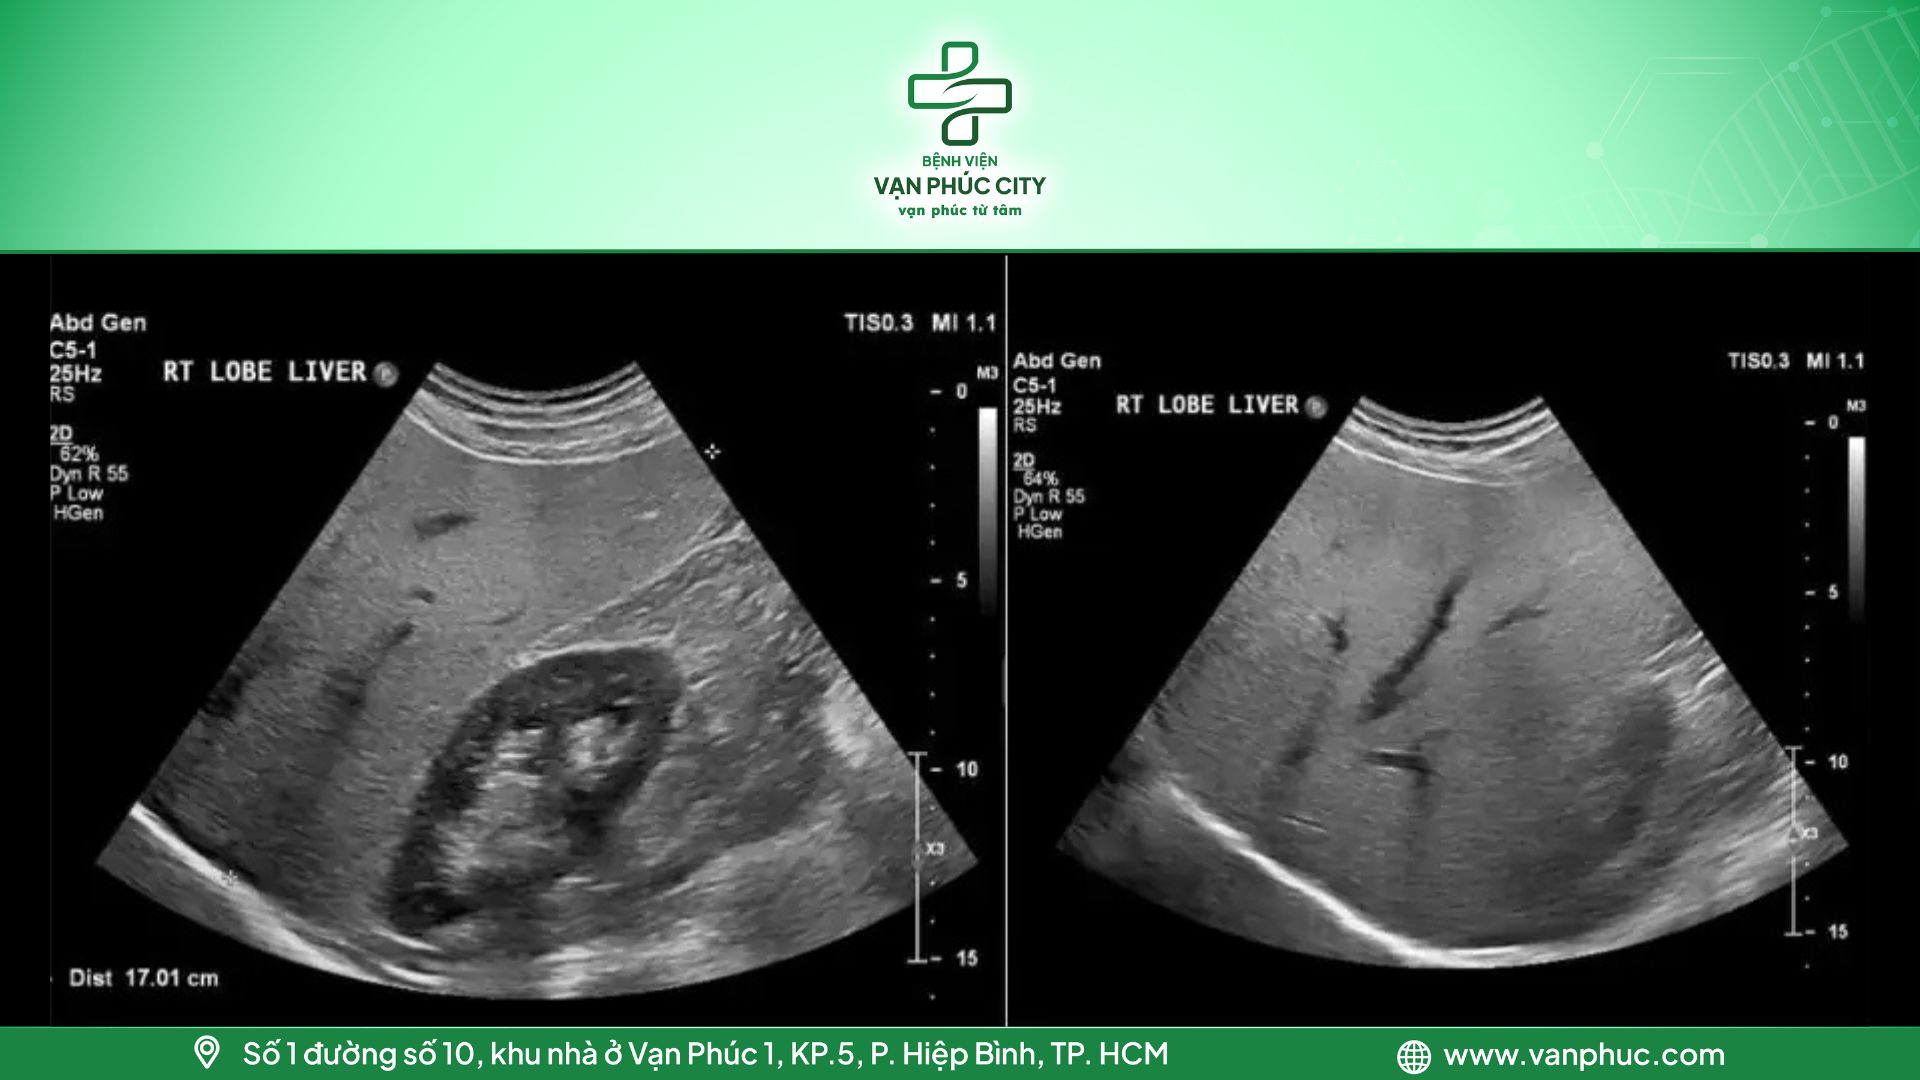

2.1. Gan nhiễm mỡ cấp độ 1

Lượng mỡ trong gan chiếm từ 5-10%. Trên hình ảnh siêu âm, vùng nhu mô gan sẽ thể hiện sự tăng âm nhẹ. Cơ hoành và các đường bờ tĩnh mạch của gan có thể mờ đi đôi chút, nhưng vẫn dễ dàng nhận diện được.

Hình 2: Gan nhiễm mỡ cấp độ 1